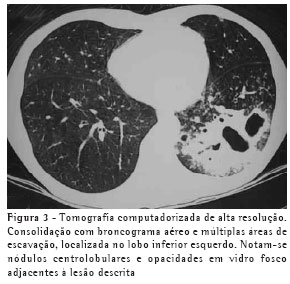

O achado de imagem mais freqüente, presente nos 7 pacientes, foi consolidação de contornos mal definidos (Figuras 1, 2, 3 e 4), sendo que 5 deles tinham broncograma aéreo de permeio, principalmente na periferia da lesão. Em 3 casos, a consolidação organizava-se sob forma de massa. Em 6 dos 7 pacientes foram observadas, no interior das consolidações, áreas irregulares de escavação, múltiplas em 5 e única em 1 paciente. Em um dos casos não se observou escavação, mas ele mostrava áreas hipodensas de permeio, sugestivas de necrose (Figura 5). Apenas um dos pacientes apresentou nível líquido no interior das cavidades.

A lesão escavada predominou nos lobos superiores, sendo 4 à direita e 1 à esquerda. Em um destes pacientes, ela acometia também o lobo médio. Em 2 casos, ela ocorreu nos lobos inferiores, 1 à direita e 1 à esquerda. Em 4 casos as lesões acometiam apenas os lobos citados, sendo portanto unilaterais. Nos outros 3, atingiam também, em menor intensidade, o pulmão contralateral. Em um caso, havia também escavação de paredes relativamente finas, multisseptada, sem nível líquido, localizada no lobo médio.

Opacidades em vidro fosco foram vistas em 6 pacientes, localizadas predominantemente ao redor das lesões escavadas, não sendo, em nenhum dos casos, achado predominante.

Pequenas opacidades nodulares centrolobulares e padrão de árvore em brotamento foram vistos em 3 pacientes, com distribuição predominantemente ao redor da área de consolidação. Em 1 destes pacientes estas lesões foram encontradas também nas porções pendentes dos lobos inferiores. Nódulos do espaço aéreo, tendendo a confluência, localizados na periferia das consolidações pulmonares, foram vistos em 4 casos.

Na nossa casuística, o principal padrão de acometimento pulmonar foi o de consolidação com broncograma aéreo de permeio e escavação, presente em 6 pacientes, sendo as escavações múltiplas em 5 casos e única em 1. As consolidações tinham grandes proporções e contornos anfractuosos. Os broncogramas aéreos estavam localizados nas porções periféricas das lesões. O lobo pulmonar mais freqüentemente envolvido foi o lobo superior direito, acometido em 4 pacientes. A maioria dos trabalhos de revisão de casos confirma tais achados.(2,5) Alguns trabalhos relatam que, embora a escavação possa não estar presente no momento do diagnóstico, ela acaba por se desenvolver durante a evolução da doença.(4) Níveis líquidos no interior das escavações foram vistos em apenas um paciente na casuística estudada.

Outros achados foram as opacidades em vidro fosco, os nódulos do espaço aéreo, os pequenos nódulos de distribuição predominantemente centrolobular, e o padrão de árvore em brotamento. Eles se localizavam predominantemente ao redor das consolidações escavadas, sendo que em um dos casos também estavam presentes em ambos os lobos inferiores. Acredita-se que tal achado deva representar disseminação broncogênica da infecção.